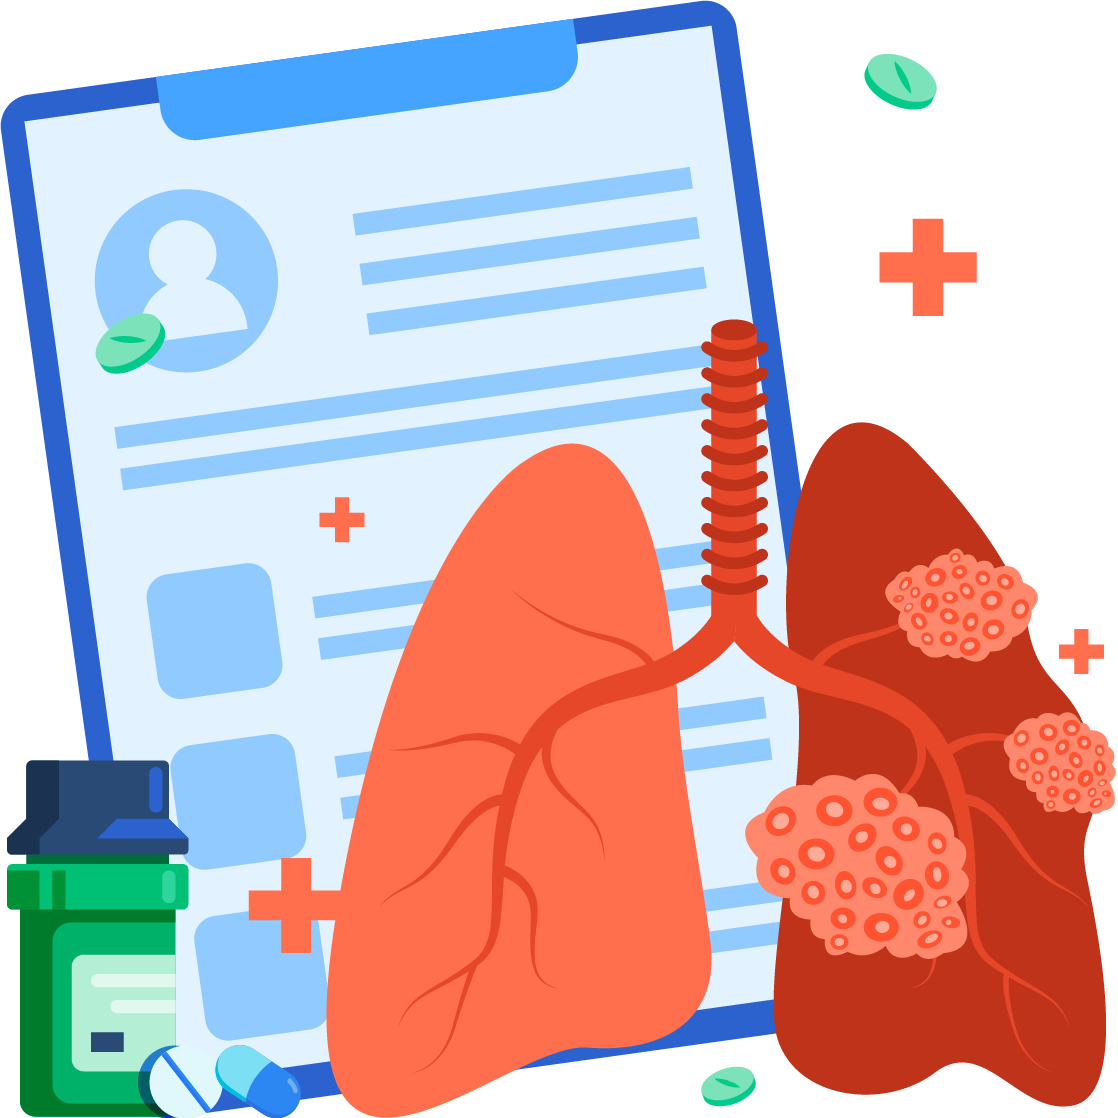

១. ជំងឺមហារីកសួត

ទោះបីជាការជក់បារីជាមូលហេតុចម្បងដែលធ្វើឲ្យកើតជំងឺមហារីកសួតក៏ដោយ អ្នកដែលស្រូបយកផ្សែងបារីក៏ទទួលផលប៉ះពាល់ដូចគ្នា។ ម្យ៉ាងវិញទៀត ជំងឺមហារីកសួតអាចបណ្ដាលមកពីការបំពុលបរិស្ថាន ប្រើប្រាស់ថ្នាំជក់ និងការប៉ះពាល់នឹងសារធាតុបង្កជំងឺមហារីក។ អ្នកដែលមានវ័យលើសពី៦០ឆ្នាំ និងធ្លាប់កើតជំងឺស្ទះផ្លូវដង្ហើមរ៉ាំរ៉ៃ ក៏អាចវិវដ្តទៅជាជំងឺមហារីកមួយប្រភេទនេះដែរ។

រោគសញ្ញា

នៅដំណាក់កាលដំបូង ជំងឺមហារីកសួតមិនបង្ហាញរោគសញ្ញាច្បាស់លាស់ក៏ពិតមែន ប៉ុន្តែគ្នាយើងអាចសង្កេតមើលសញ្ញាទាំងនេះ។

- ក្អក

- ដកដង្ហើមខ្លីៗ

- ស្អក

- ឈឺទ្រូង

- ដកដង្ហើមលឺខ្លាំងៗ

- កំហាកប្រែប្រួល

វិធានការការពារ៖ បញ្ឈប់ការជក់បារី និងនៅឲ្យឆ្ងាយពីផ្សែងបារី។